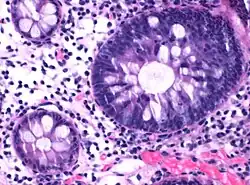

| Micrograph of hyperplastic polyp | |

Histopathology

Histopathologically, there are two main types of hyperplastic polyps, which have genetic differences, as well as different histologic structure, but no significant differences clinically.[4] The two main types of hyperplastic polyps are microvesicular mucin-rich type and goblet cell-rich type.[1] A mucin-poor type with eosinophilic cytoplasm, which is rare, was previously described.[4] However, the mucin poor type is no longer considered a distinct subtype.[1]

Mucin-rich type

The luminal portion has a serrated ("saw tooth") appearance formed by tufts or folds of abundant apical cytoplasm. It contains glands with star-shaped lumina.[4] There are crypts that are elongated but straight, narrow and hyperchromatic at the base. All crypts reach to the muscularis mucosae.[4] The basement membrane is frequently thickened.[4]

Goblet cell-rich type

Elongated, fat crypts and little to no serration. Therefore, they may not be obvious without comparing to adjacent normal intestinal wall.[4]

They are filled with goblet cells, extending to surface, which commonly has a tufted appearance.[4]